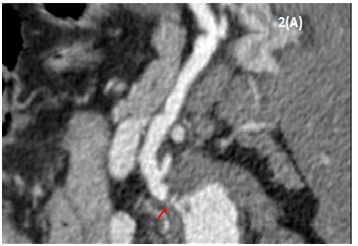

In multidisciplinary assessment, our hepato-bilio-pancreatic radiologist highlighted a periampullar resectable tumor and a celiac axis significant stenosis. Diagnostic angiography was then performed, which confirmed the celiac axis stenosis and revascularization was attempted, but proven to be technically infeasible. Surgical resection was decided. Intraoperative hepatic artery flow was severely compromised with GDA occlusion, confirming the celiac axis stenosis. A supra-celiac-aorto-hepatic bypass graft (uni-graft K-DV 8mm) followed by a cephalic duodenopancreatectomy with a dunking pancreato-jejunostomy, end-to-side hepatico-jejunostomy and piloro-jejunostomy was performed (Figures 3 & 4).

Figure 3 Hepatic artery arteriotomy.

Figure 4Aortic-hepatic bypass graft.